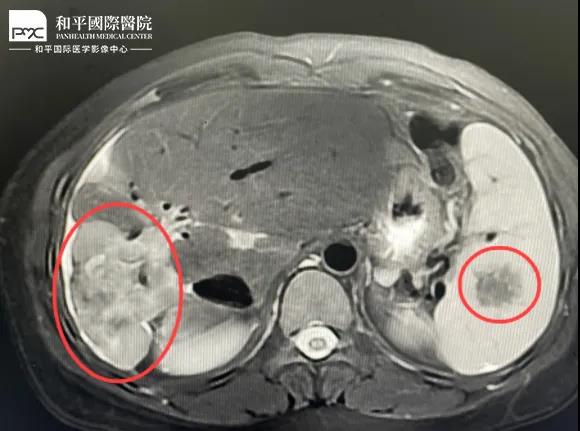

檢查結(jié)果對于這家人而言猶如晴天霹靂,經(jīng)核磁共振等相關檢查,當?shù)蒯t(yī)生懷疑是肝癌,建議手術治療。悲痛中,家人們對這樣的結(jié)果表示無法接受,想要多去幾家醫(yī)院看看,為了進一步確診,王小姐來到我院醫(yī)學影像中心進行檢查,事情竟發(fā)生了戲劇性反轉(zhuǎn)。

根據(jù)影片分析,結(jié)合王小姐有系統(tǒng)性紅斑狼瘡的病史,長期服用激素,免疫力低下,近期又有低熱盜汗的癥狀,影像中心執(zhí)行主任侯文杰初步判斷王小姐是得了肝結(jié)核,并不是肝癌!

由于肝結(jié)核是臨床非常少見的病例,單靠影像診斷是很難診斷正確的,在侯主任的建議下,王小姐做了穿刺活檢,診斷結(jié)果的確是肝結(jié)核。